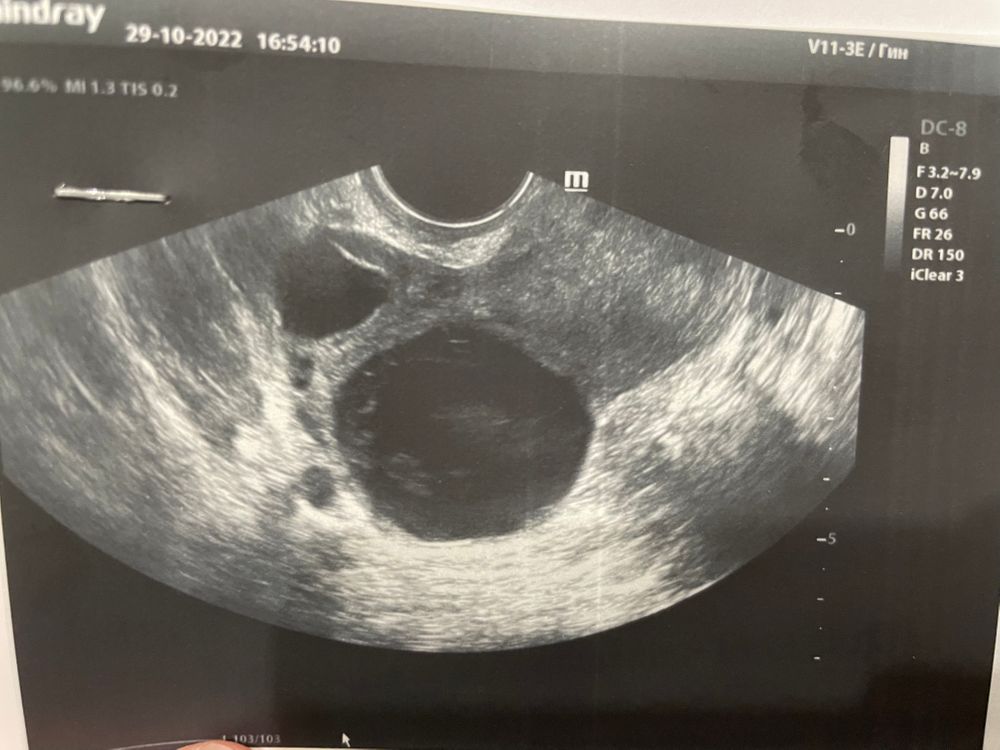

По фото похоже на кисту желтого тела. Сантиметра 3-4 мм. Кровоток нужно смотреть. Раз описано как желток тело, доктору с датчиком в руках виднее. Чем по фото

ТыКатя, авоскулярные оба написано. Врач узи была не очень компетентна, мне не понравилась. Поэтому перепроверяю инфу

Victoria, тогда надо смотреть последнее узи. Как давно Оно сделано. Какой день цикла. Желтое тело кровоток дает в любом случае. Интенсивность зависит от его «старости» может с прошлого цикла осталась киста,тогда без кровотока. Эндометриоз и кисты желтого тела почти неотличимы. В этом случае надо смотреть в динамике после менструации. Кисты желтого тела рассасываются за цикл-два. Узи очень субъективно. Вопрос насмотренности врача и кто он по первичной специальности. Гинекологи понимают что смотрят, терапевты и прочие неочень

ТыКатя, вот узи в начале месяца. Тогда на 19 дц пришли М. Не было ничего подобного Изображение

ТыКатя, и вот описание сегодняшнего узи Изображение

Victoria, ну раз этого не было в рамках одного цикла и яичники были без образований. То сейчас это киста желтого тела. Рядом или регрессирующий фолликул либо вторая овуляция. Странно что пишет аваскулярное конечно. Но овуляция точно была.

Victoria, ну судя по узи у вас 2 кисты фоликулярная и жт

Victoria, ну в узи написано аваскулярнрное, значит киста. Это легко проверить, сдайте прогестерон. Если он очень высокий, значит это киста

Я не вижу тут ЖТ(

Victoria, вижу фолликулярную кисту и преовуляторный ДФ, возможно просто в регресс уходит и уже деформирован.